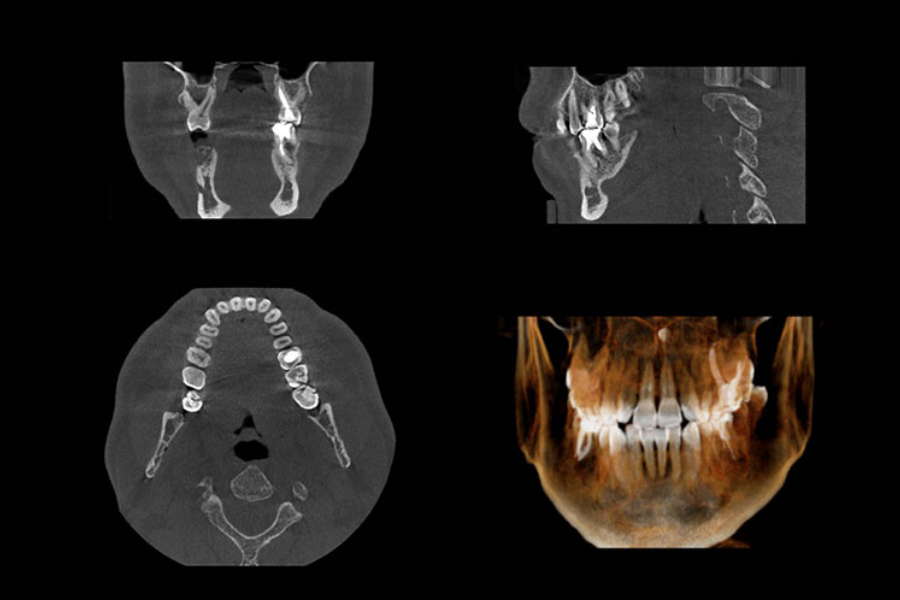

Sự thật: Sâu dưới chân răng là khu vực tập trung nhiều dây thần kinh quan trọng nên điều lo lắng này cũng không hoàn toàn không có căn cứ. Nhưng các bạn đừng lo, trước khi nhổ răng các bác sĩ sẽ thăm khám lâm sàng trong miệng ( hình thể, độ nghiêng, chiều cao,..) rồi sau đó chỉ định cận lâm sàng bao gồm: xét nghiệm và chụp phim. Với công nghệ hiện đại ngày nay, các bạn sẽ được chụp phim x-quang toàn hàm ( panorama), phim 3D (phim CT Conebeam) “soi đến tận chân tơ kẽ tóc” sẽ giúp bác sĩ xác định răng của bạn có dần dây thần kinh không, nhổ có khó không,…Hơn nữa, với những dụng cụ, máy móc hiện đại, việc nhổ răng trong chỉnh nha thường được coi là một tiểu phẫu tương đối đơn giản và an toàn, hầu như không ảnh hưởng gì đến sức khỏe của bệnh nhân.